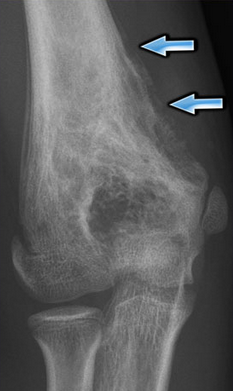

A 15 year old boy presents with pain, swelling and lack of mobility in the knee. What do you see in this x-ray and what condition does it hint towards?

Note Codman’s Triangle evident by destruction of the cortex which shows malignancy. This hints toward osteosarcoma.

Why is a tissue sample not enough to make a diagnosis of osteosarcoma?

Osteoblasts intimately associated with the osteoid they are making is typical of osteosarcoma AND bone fractures.